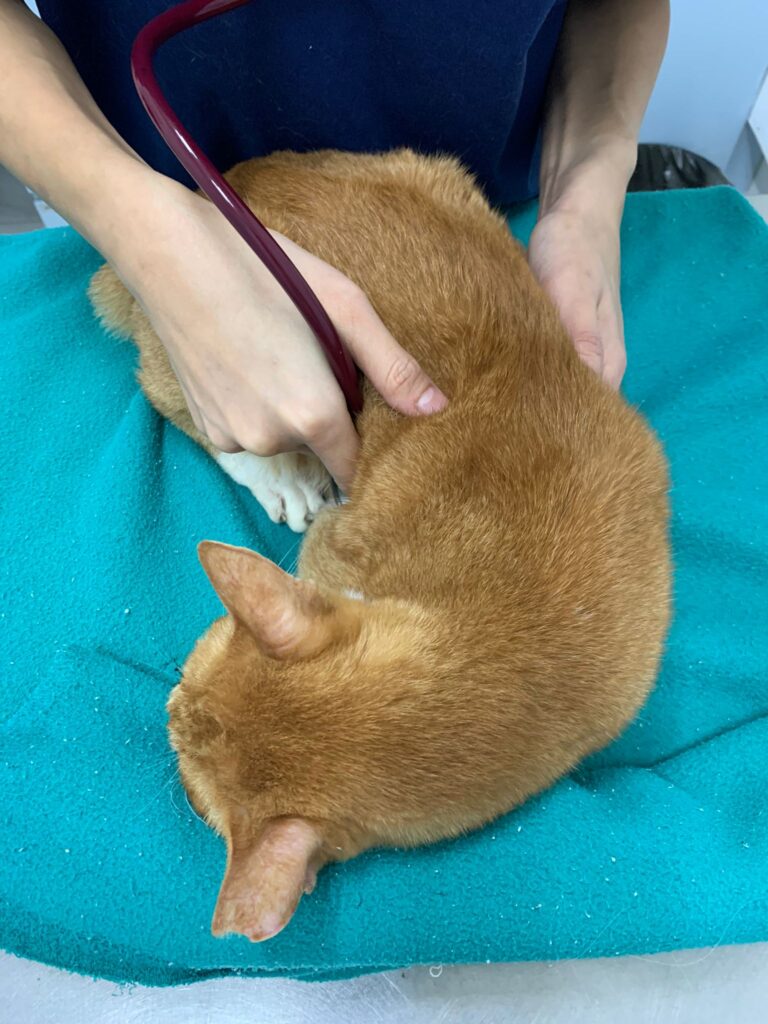

11Am+: 4.23kg – gain 740g in 12 days cos eating well but this morning I serve he did talk away but did eat the aixia oldie and etc b4 we leave house for Dr Nally

Can hear gallop rym – consistent w the hr taken 204. Bp average 191. But clinic damn noisy cos of hacking sound above.when the sound stop rehear again, the heart ok. Anyway last time taken pro bnp le, negative.

To take Cbc. Blood taken from his left jacular – easy and steady.

Cbc out: Eos high again – dr wants him to be dewormed. Hct 26.9%, going up, wbc 20.35 going down doxy to continue for total 21 days.

Back and I Subcut him, his body looks big N hard and muscular. Erm ….

Got heart mur mur – taken probnp then

HR 240

Stomach so far ok.

Gum pale

To taken Cbc, Chem 15, lytes, probnp, pancreatitis.

Taken bp using from right leg.

His bp at resting is abnormality high. But can due to heart, kidney or ???

Can also use Cerenia nose drop on him, cos his is upper respiratory issue.

He looks v weak when in carrier.

He needs to take full UA.

So what’s the med he needs to be on for his high bp?

Results: probnp normal. So mur mur due to anemic?

Pancreatitis abnormal, sigh can’t send out for quantatitis cos no more bloods at clinic. Kns siak. Told clinic send out rena blood as didi for the quantative test. – confirmed

Didi slight high on glucose. Should be stress.

anemic for sure. HCT 21% plus I’ll start him on darbepoetin for sure too. Now is he needs ab? Waiting for dr nally to send summary.